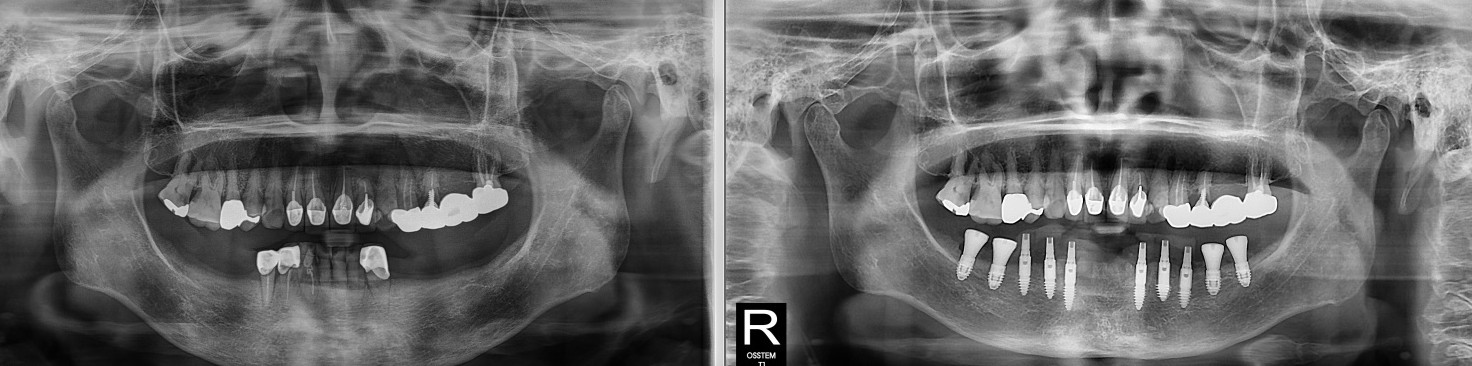

이분 같은 경우

아래 앞니는 염증으로 인해

이미 흔들리고 있었고

양쪽 어금니는

오래전에 소실된 상태였습니다.

겉으로 보기에도

잇몸이 많이 부어 있었지만,

엑스레이 사진상에서도

치조골이 상당 부분 소실된 것

확인되었습니다.

환자분의 엑스레이를 보면

‘칼릿지(Crest)’라고 불리는

잇몸뼈 부분이 거의 사라져 있었습니다.